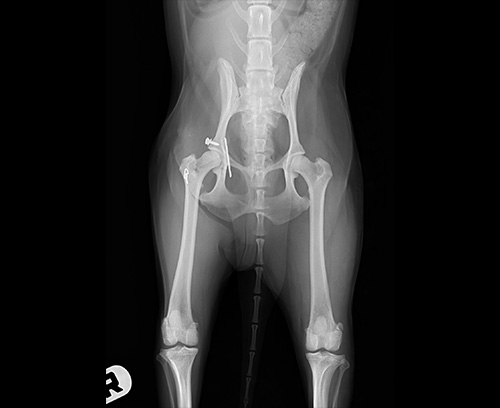

股関節形成不全

股関節脱臼(整復後)

股関節脱臼